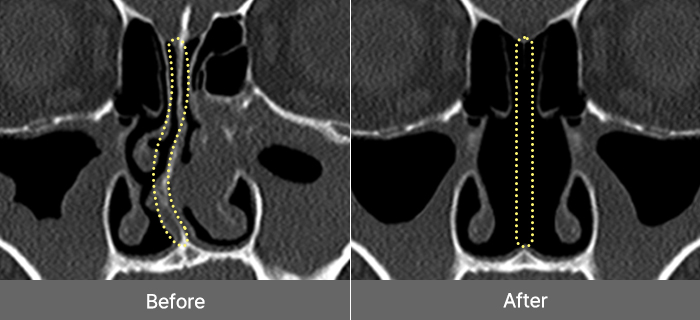

Deviated Nasal

Septum

A deviated nasal septum

occurs when

the cartilage

located at the center of

the nose bends, causing

functional

issues such

as nasal congestion,

rhinitis, and sinusitis.

Treatment Points

Remove the curved septal

cartilage and bone, then

straighten the septal

cartilage

to correct the

shape properly.

Dual Correction from the Inside Out

Straightening the Nose Bridge and Improving Nasal Congestion!

Functional rhinoplasty addresses both the functional issues of nasal disorders, such as correcting misaligned

cartilage and reducing enlarged mucosa, and the aesthetic aspects of refining the nose’s shape, providing comprehensive

improvement from the inside out.